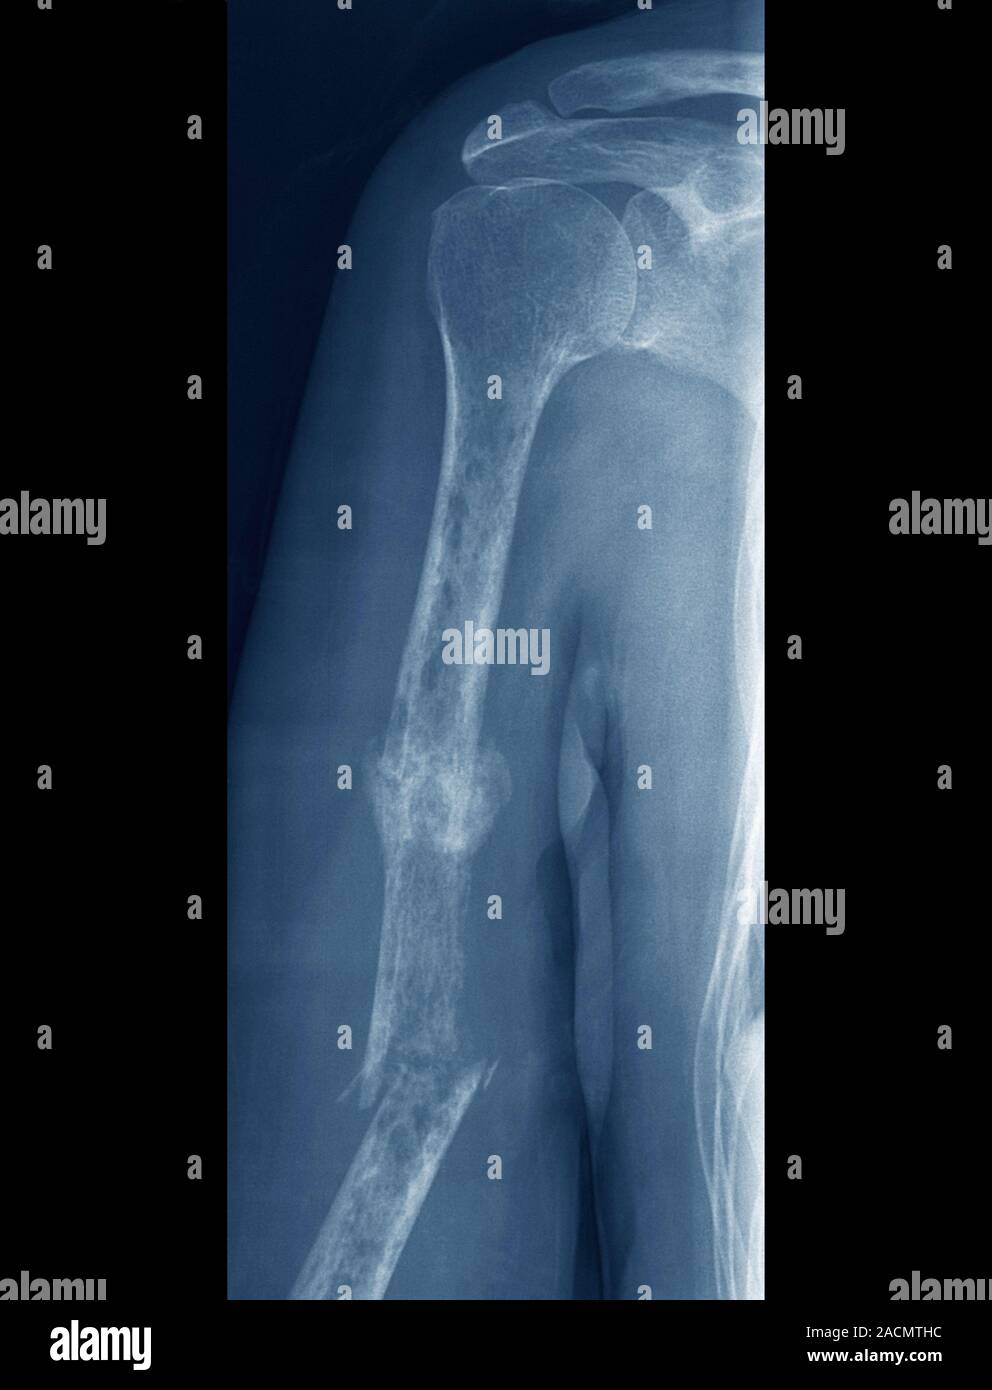

From www.alamy.com

Fractures and bone cancer. Frontal Xray of the right arm of a 63year Pain In Forearm Bone Cancer At first, this pain might come and go and might. Pain (usually worse at night). It may get worse when a person uses the bone, such as when someone with a tumor. The most common symptom of bone cancer is pain in a bone or joint that doesn’t go away and may be made worse by exercising. The most common. Pain In Forearm Bone Cancer.